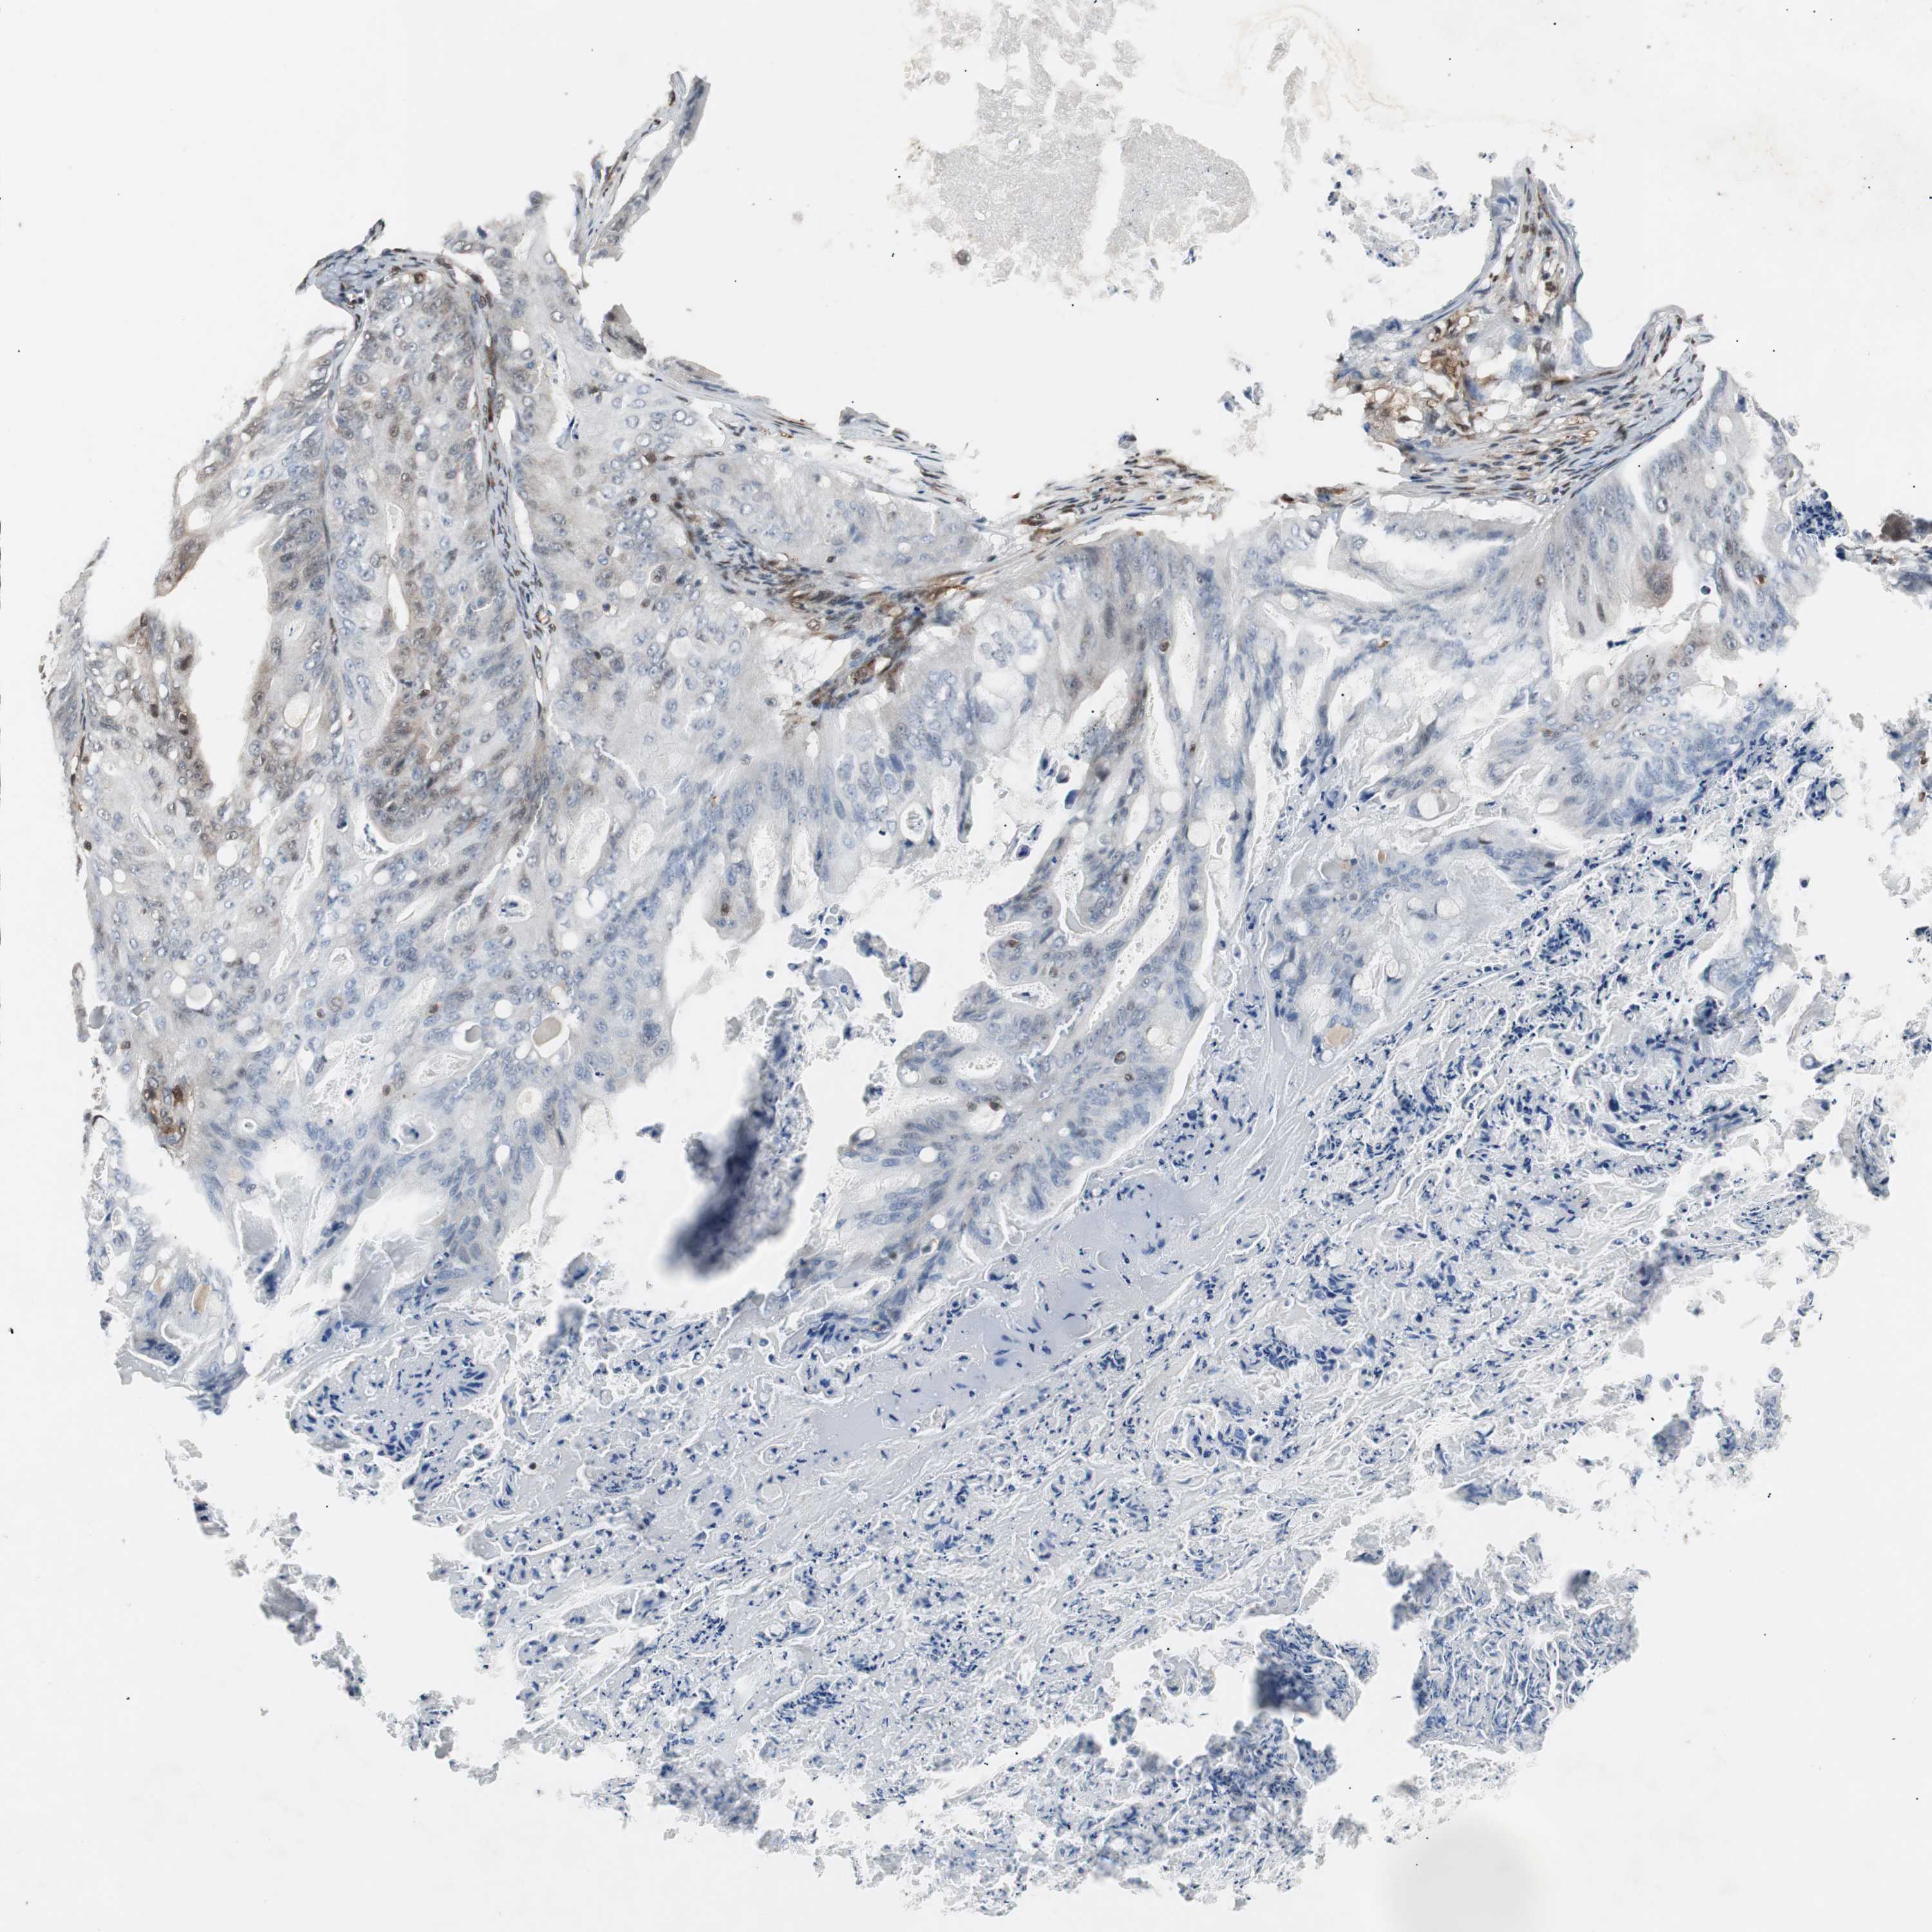

OVARIAN CANCER - Protein expressioni

A mouse-over function shows sample information and annotation data. Click on an image to view it in a full screen mode. Samples can be filtered based on level of antibody staining by selecting one or several of the following categories: high, medium, low and not detected. The assay and annotation is described here.

Note that samples used for immunohistochemistry by the Human Protein Atlas do not correspond to samples in the TCGA dataset.

Antibody stainingi

Antibody staining in the annotated cell types in the current human tissue is reported as not detected, low, medium, or high, based on conventional immunohistochemistry profiling in selected tissues. This score is based on the combination of the staining intensity and fraction of stained cells.

Each image is clickable and will lead to virtual microscopy that enables deeper exploration of all samples and also displays staining intensity scores, fraction scores and subcellular localization as well as patient and tissue information for each sample.

HPA022434

HPA022953

HPA022959

HPA028758

CAB007783

Staining

Cystadenocarcinoma, serous, NOS

Carcinoma, endometroid

Cystadenocarcinoma, mucinous, NOS

Carcinoma, NOS